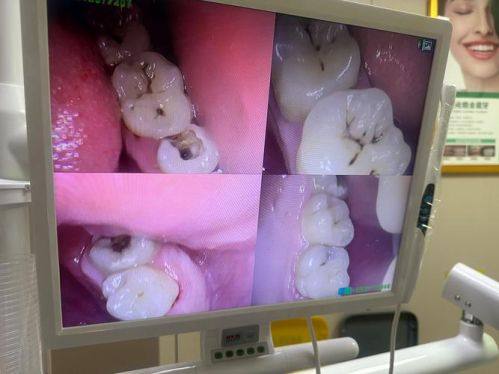

口腔局部感染重度的儿童

当孩子口腔局部感染重度时,也不适合马上补牙。比如牙齿周围有重度的牙龈脓肿、根尖周炎等情况。在感染没有得到有效控制的情况下补牙,可能会导致感染进一步扩散,加重病情。此时,应该精良行抗感染治疗,等炎症消退后,再进行补牙。这样可以确保补牙的成效,也能避免感染对孩子口腔健康造成更重度的影响。